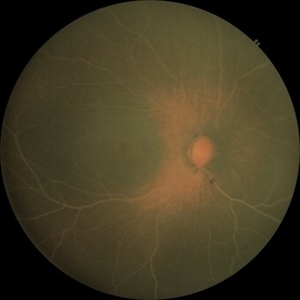

Idiopathic Intracranial Hypertension Idiopathic Intracranial HypertensionDec 11 2022 by Anjana Mirajkar, MS Ophthalmology Central colour photo of RE of a 23 year old male case of Idiopathic Intracranial Hypertension Photographer: Dr. Anjana Mirajkar -Retina Foundation, Ahmedabad Condition/keywords: benign idiopatic intracranial hypertension